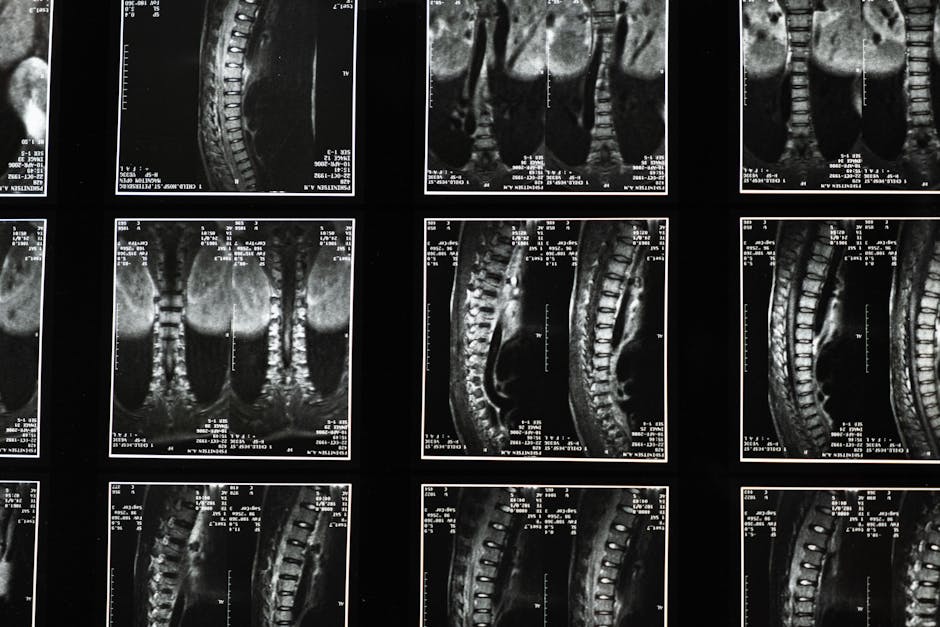

X-ray analysis and instrumentation provide objective data for your treatment plan.